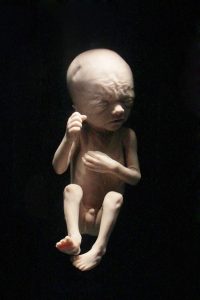

O bebê com 6 meses já está exatamente do jeitinho que estará no dia do nascimento, mas ainda com baixo peso. Ele já tem tudo formado, inclusive cílios e sobrancelhas, que proporcionam sua fisionomia completa. Agora o seu foco é o ganho de peso que irá aumentar em torno de 500 gramas por semana a partir de agora.